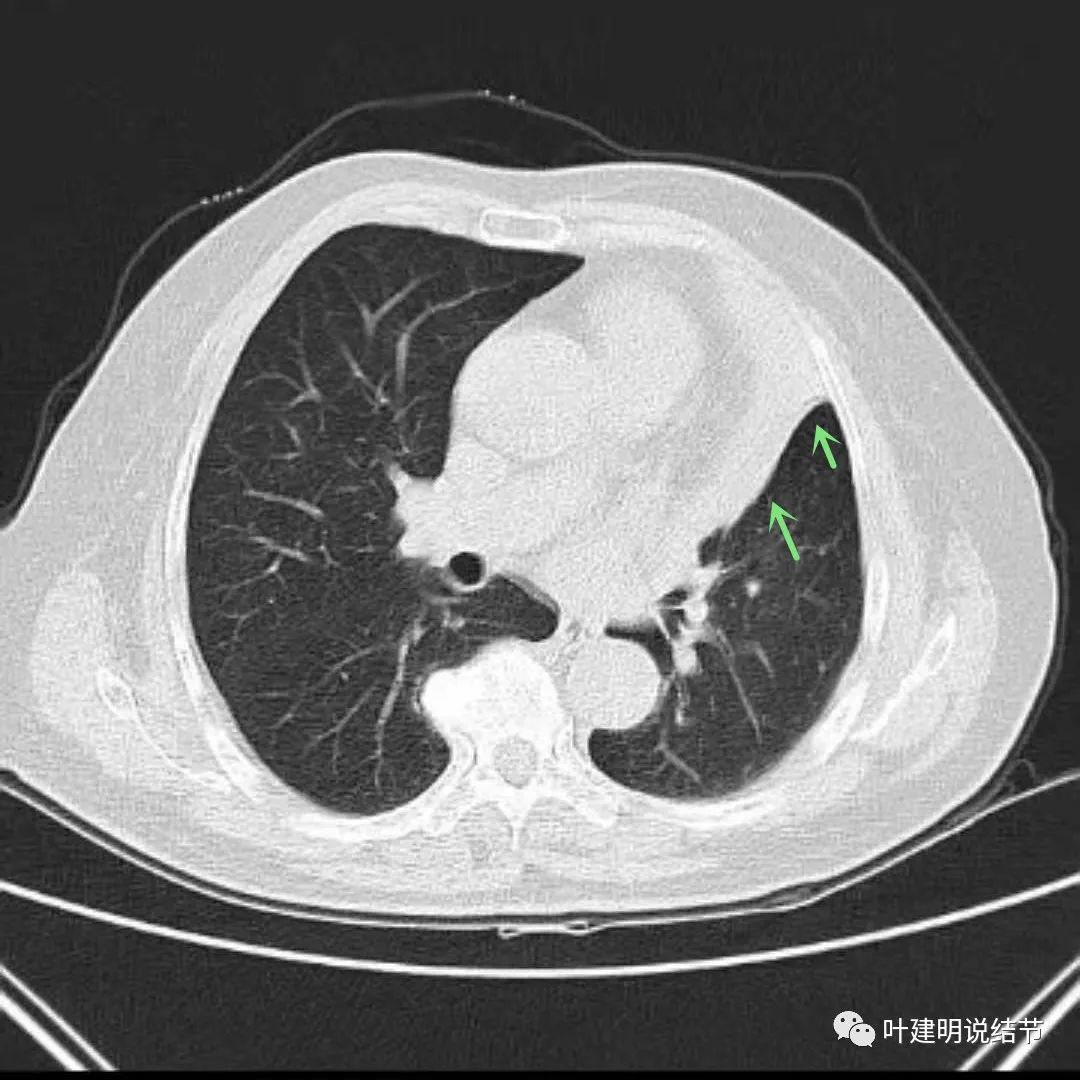

上图绿色箭头所指区域考虑为肺不张,红色示肿瘤处,蓝色箭头示左下叶支气管

上图绿色箭头所指区域考虑为肺不张,红色示肿瘤处,桔色箭头所指处是叶间肺动脉。蓝色箭头示左下叶支气管管腔

上图红色箭头示肿瘤,绿色箭头示肺不张